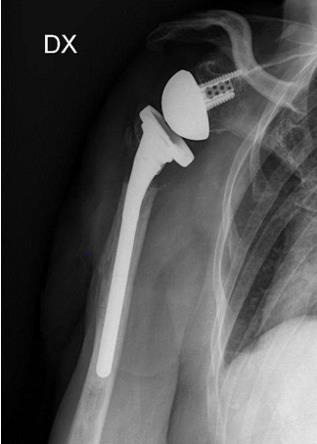

A 69-year-old woman came to ER of Poliambulanza of Brescia in October 2019. X-rays were obtained. Fracture involved proximal humerus of the right, dominant, upper arm. The fracture was 11C3.1 according to AO classification. At first, the fracture was treated with an external. fixation using a Galaxy EF in the first twenty-four hours. The EF was removed after one month because of the loss of reduction with displacement of the fracture. Physio- kinesitherapy was indicated but she was unable to underwent to treatment. She was lost at follow -up for several months due to COVID-19 pandemic and the social limitations that resulted. After 7 months, Xrays showed a dislocated nonunion of proximal humerus with necrosis of the head. She complained shoulder pain with passive elevation of 40° and scapular dyskinesia. In March 2021 she was listed for a reverse shoulder arthroplasty. During the surgery, Synovasure test and white blood cell count were performed: both tested negatives. A cemented trauma stem “Equinoxe” by Exactech number 8 mm was applied with a standard baseplate fixed with three screws of 26, 18, 18 mm. External rotators were reinserted, and range of motion (ROM) was good at three months follow-up.

Radiographic checks showed a partial loss of reduction and physio-kinesitherapy was indicated but she was unable to underwent to treatment because of the new social restrictions. Further radiographs showed gradual loss of reduction. Therefore, we started contemplating a definitive treatment by performing a ORIF with bone graft or a shoulder arthroplasty, but at that moment, the patient was lost at follow-up. Given the poor bone quality, after the removal of the EF, we would probably have implanted a hemiarthroplasty or a reverse prosthesis with a press-fit primary humeral stem fixation, considered an optimal choice because of the possible easier revision, decreased operative time, healing time, and resolution of the symptoms [16]. After 7 months, the patient came back to our department, suffering from pain and severe functional limitation, compounded by a preternatural movement of the joint. Radiographs showed evident dislocated nonunion with reabsorption of tuberosities and metaphysis.

Therefore, our choice has been to implant a reverse shoulder prosthesis with a cemented trauma stem “Equinoxe” by Exactech number 8 mm. This choice involved several compromises like technical difficulties due to the severe bone loss and higher risks of dislocations, infections, nerve injuries and thromboembolism due to the use of cement, compared to an arthroplasty with a pressfit stem [17-20]. At three-month follow-up, the patient showed no pain and a sufficient function of the joint. Since the exact amount of loss to follow-up is not valuable, there is a chance that cases of nonunion in longstanding fractures like this could increase in the near future. Our experience shows that cemented stem fixation can be an important choice of treatment for these patients. Other strategies, like telemedicine, should be considered and eventually implemented to prevent this kind of consequences resulting from the pandemic [21-23].